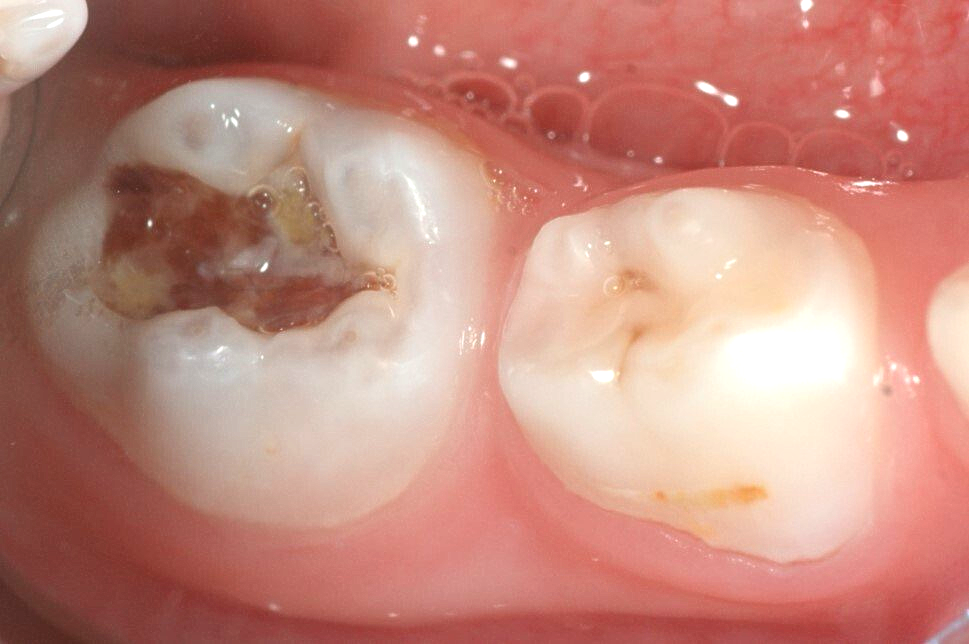

Schritt 2: Diagnostisches Röntgenbild - immer obligatorisch; die Karies (dunkel) ist tief und sehr ausgedehnt